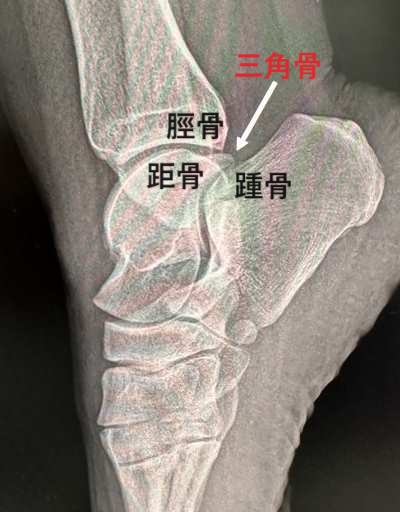

三角骨障害 足関節後方インピンジメント症候群

三角骨とは、足関節の距骨の後ろにある過剰骨(副骨)のことです。健常者の10%程度に認められます。一般的に三角骨があっても日常生活に全く支障がありませんので無症候性三角骨と呼ばれます。

三角骨障害とは、三角骨を有する方が足首を強く下に蹴るスポーツ(サッカー、水泳、剣道、空手など)や、つま先立ちを繰り返す(バレエダンサーなど)の動作によって

三角骨が脛骨後部と踵骨(かかとの骨)に挟まれてアキレス腱の深部に強い痛みを訴える疾患です。別名、足関節後方インピンジメント(衝突)症候群とも呼ばれます。全ての年齢に起こりますが、若者に多く認めます。

レントゲン検査です。癒合不全のタイプ骨折のタイプがあります。また、検査として三角骨周辺の圧痛部に局所麻酔を打つと症状が改善されるので容易に診断できます。